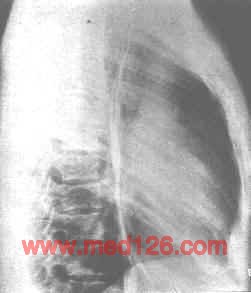

纵隔支气管囊肿。胸片正位(上图)示肿块位于右侧纵隔,贴于主动脉弓及右心缘。侧位(下图)示肿块主要位于中纵隔中部,重叠于心影上。

①囊肿呈圆形或卵圆形肿块,多位于中纵隔的上、中部,好发于气管两旁或气管分叉处。

②密度均匀一致,边缘光滑、整齐。

③囊肿张力低,贴附于气管部分可变扁。张力高时,气管可受压。偶尔与气管相通,出现气液平面。